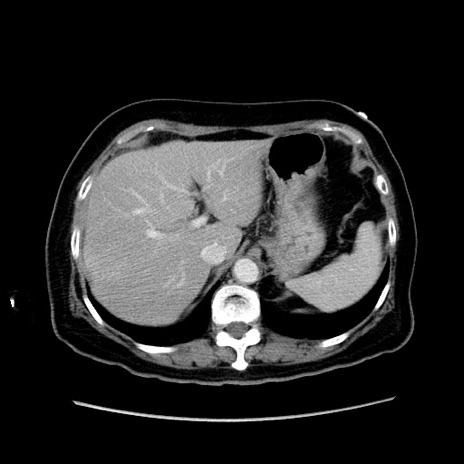

症例19(横断像)

【症例】80歳代女性

【主訴】下腹部痛

【現病歴】約8時間前より下腹部痛の出現あり、救急外来受診。

【既往歴】両側付属器切除

【身体所見】意識清明、下腹部正中に手術痕あり、その部位に一致して圧痛と反跳痛あり。腸蠕動音は亢進。

【データ】WBC 9300、CRP 0.15